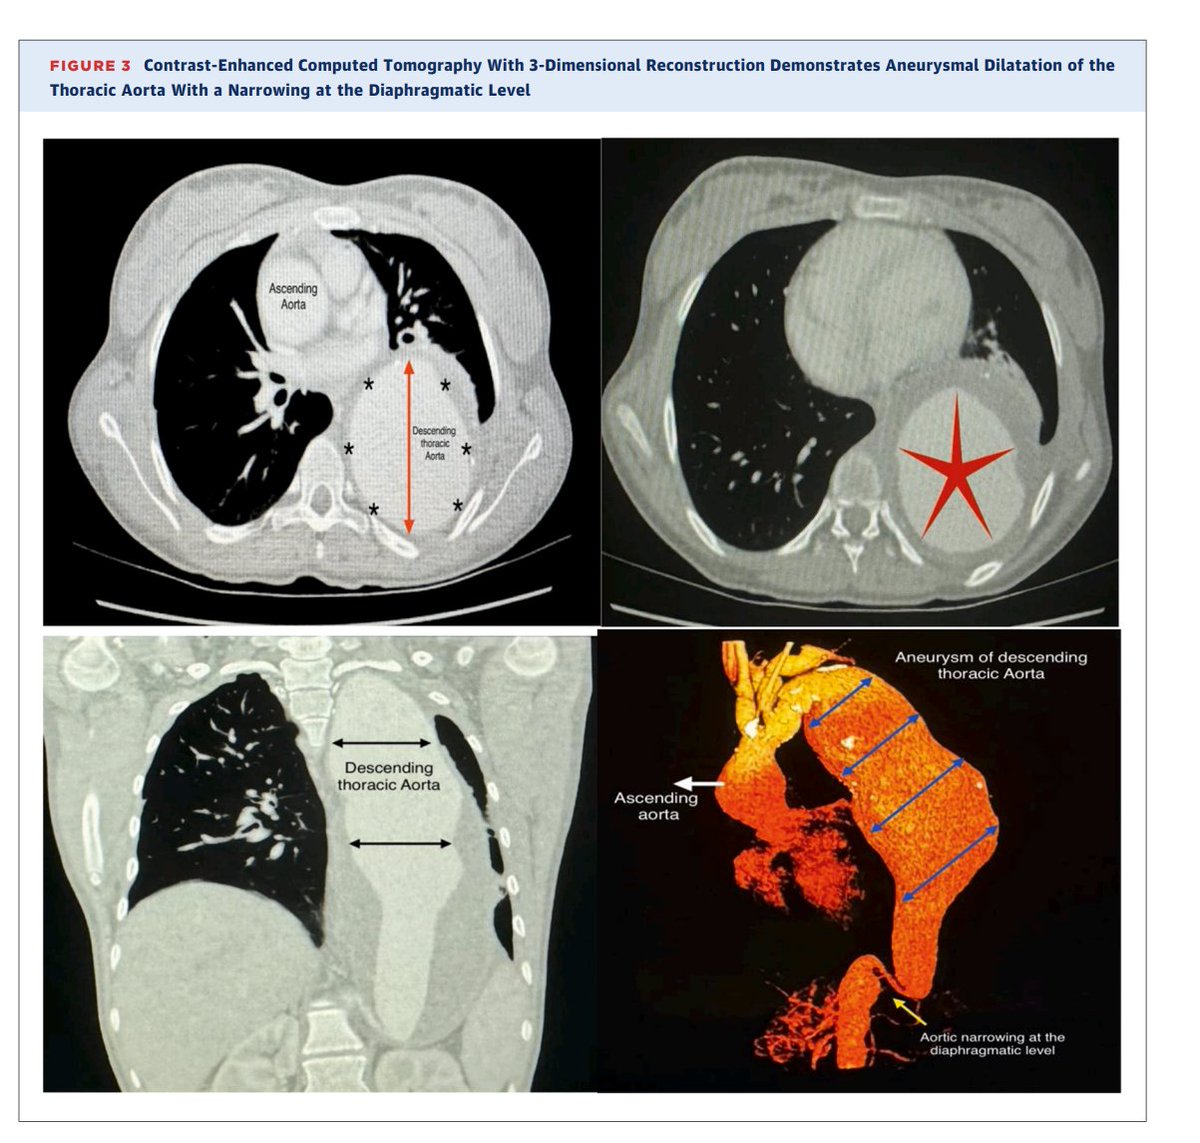

Arterial aneurysms are among the rare vascular manifestations of HIES. We present a case of a 17-year-old girl who had a known history of HIES since childhood. She had a large thoracic descending aortic aneurysm, which required surgical repair to prevent complications

Hyperimmunoglobulin E syndromes (HIES) are a heterogeneous group of primary immunodeficiencies sharing manifestations including recurrent lung infection and significantly raised serum levels of immunoglobulin E.

New publication, JACC case reports A Huge Thoracic Aortic Aneurysm as a Rare Complication of Hyperimmunog... https://t.co/iiAyH7bCaE